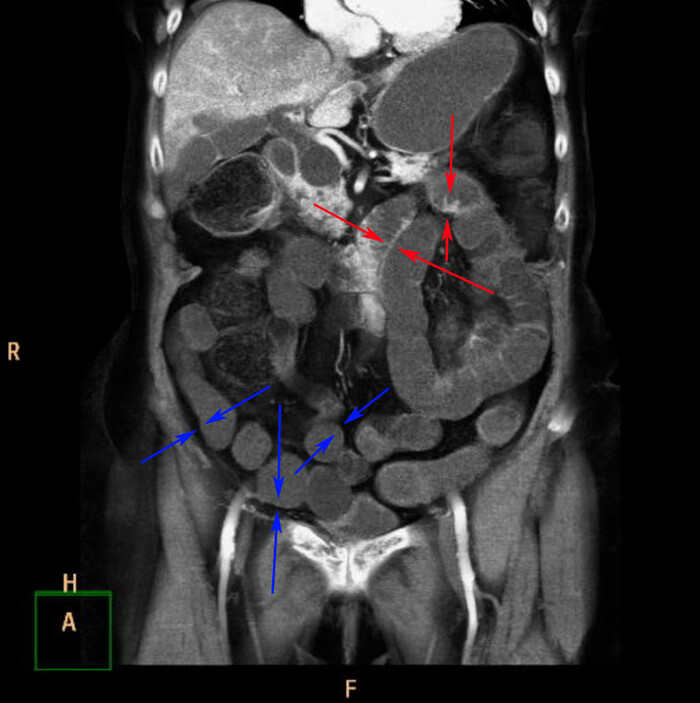

По КТ в мягкотканном окне (специальные настройки яркости и контраста для лучшего отображения мягких тканей) определялись увеличенные лимфатические узлы в средостении справа паратрахеально, в области корня правого лёгкого и инфракаринально (ниже места "разделения" трахеи на правый и левый бронх):

1 и 2: аксиальные срезы, 3 - корональная реконструкция; лмф.узлы - красные стрелки

В лёгочном окне - очаги консолидации ("уплотнения" лёгочной ткани) в постеробазальных (задне-нижних) отделах правого лёгкого (на ренгенснимках и КТ, а также МРТ та часть, что на мониторе расположена слева - всегда правая сторона пациента). На последнем снимке серии ниже (сагиттальная или боковая реконтрукция) были непонятные артефакты, как от металла:):